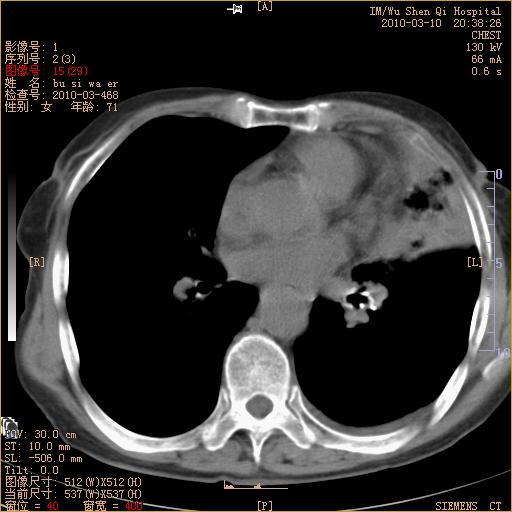

以下是引用随光逐影在2010-3-11 0:41:00的发言:[br]1)考虑左肺及右肺上叶继发性肺结核并左肺炎症感染。2)左侧支气管内膜结核可能;建议必要时行纤支镜检查。3)肺气肿。4)心包膜增厚(或少量心包积液)。5)左侧胸腔积液。